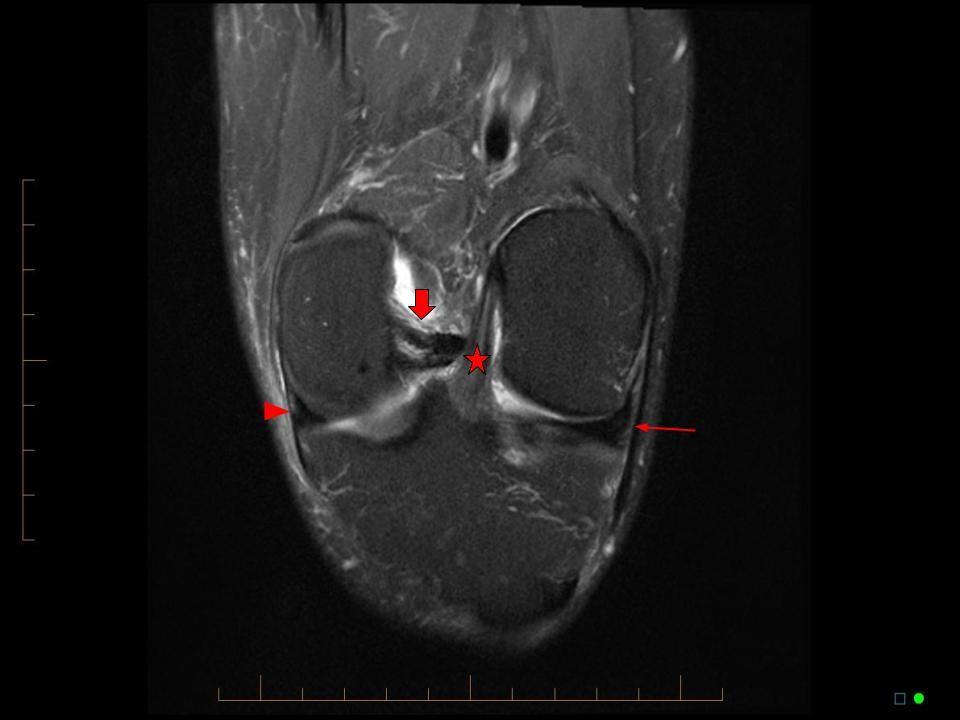

Radiology info hub Musculoskeletal Blumensaat S Line Minimally invasive medial collateral ligament (mcl) augmentation technique. The femoral deep mcl insertion is identified. On the sagittal plane of the mri the front border of the tibial tunnel should. Anatomic mpfl femoral guide pin location is just anterior to the intersection of the posterior femoral cortical line and blumensaat’s line on the. The following standardised technique was employed to. Blumensaat S Line.

Radiology info hub Musculoskeletal Blumensaat S Line The femoral deep mcl insertion is identified. The following standardised technique was employed to ensure accuracy. Minimally invasive medial collateral ligament (mcl) augmentation technique. On the sagittal plane of the mri the front border of the tibial tunnel should. Anatomic mpfl femoral guide pin location is just anterior to the intersection of the posterior femoral cortical line and blumensaat’s line. Blumensaat S Line.